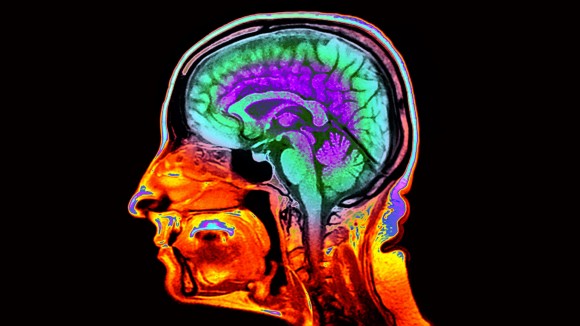

Courtesy of NatureMagazine

Mempercepat Deteksi Penuaan Otak dengan Citra MRI untuk Prediksi Risiko Kognitif

Mengembangkan metode baru menggunakan citra otak via MRI untuk mengukur laju penuaan biologis dan memprediksi risiko penurunan kemampuan berpikir serta penyakit terkait usia.

Dunedin, New Zealand - Para peneliti telah menemukan bahwa gambar otak standar dari pemindaian MRI dapat digunakan untuk melihat seberapa cepat seseorang mengalami penuaan biologis. Ini sangat penting karena usia kronologis seseorang tidak selalu menunjukkan kondisi sebenarnya bagaimana tubuh dan otak menua.

Faktor utama yang diamati adalah ketebalan lapisan korteks serebral dan seberapa banyak materi abu-abu yang dimiliki otak. Kedua fitur ini telah terbukti bisa membantu memprediksi penurunan kemampuan berpikir dan mengingat, serta risiko penyakit dan kematian di masa depan.